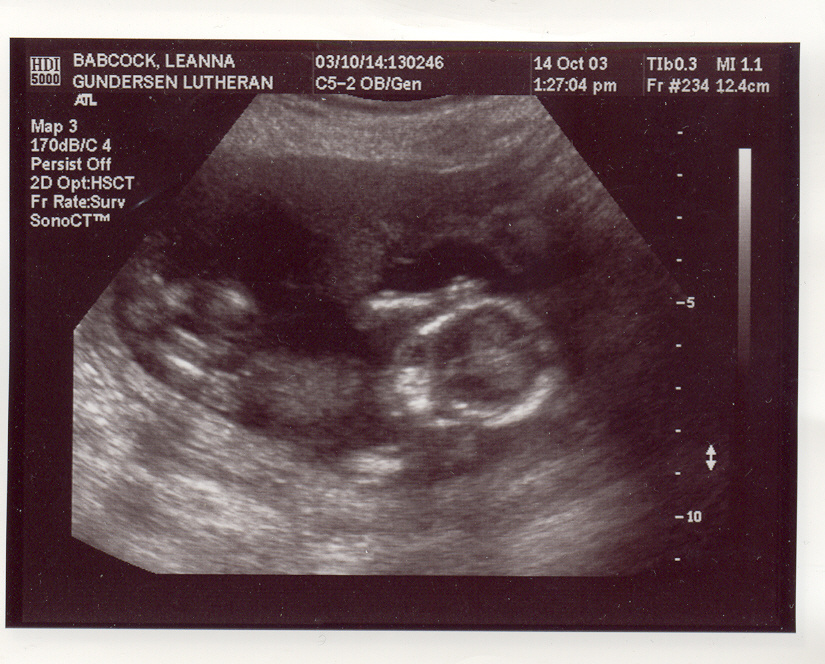

This is my new baby page. I am due at the end of March/start of April, 2004. Here are my first ultrasound pix. They may take a few minutes to load, so be patient. These ultrasound pix were taken Oct. 14th, 2003. We were unable to find out the sex of the baby because it was too early in my pregnancy and also the baby's umbilical cord was between it's legs, and whenever we tried to see what was down there that was blocking our view, and also the baby would put it's hands in the way. I go in for another ultrasound on Nov. 11th. I will post more pix up after then. The baby seems to be healthy at this point and Aidan and I are very excited and preparing for our first child with joy in our hearts! :)